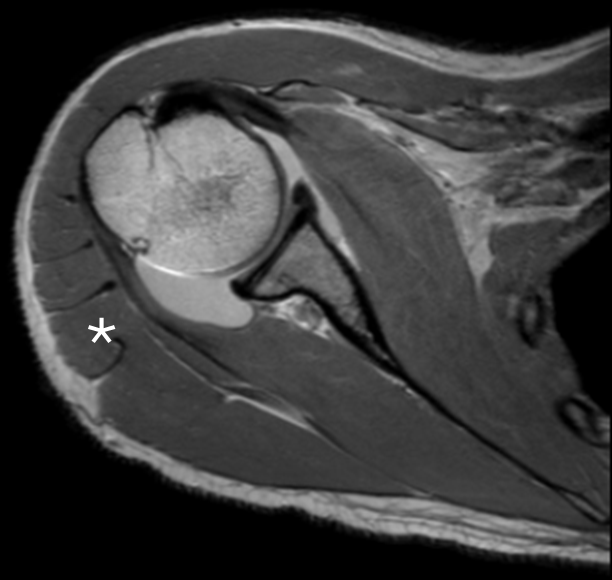

2.128 Welcher der folgenden Nerven trägt typischerweise zu der Innervation mit dem Stern markierten Muskel bei?